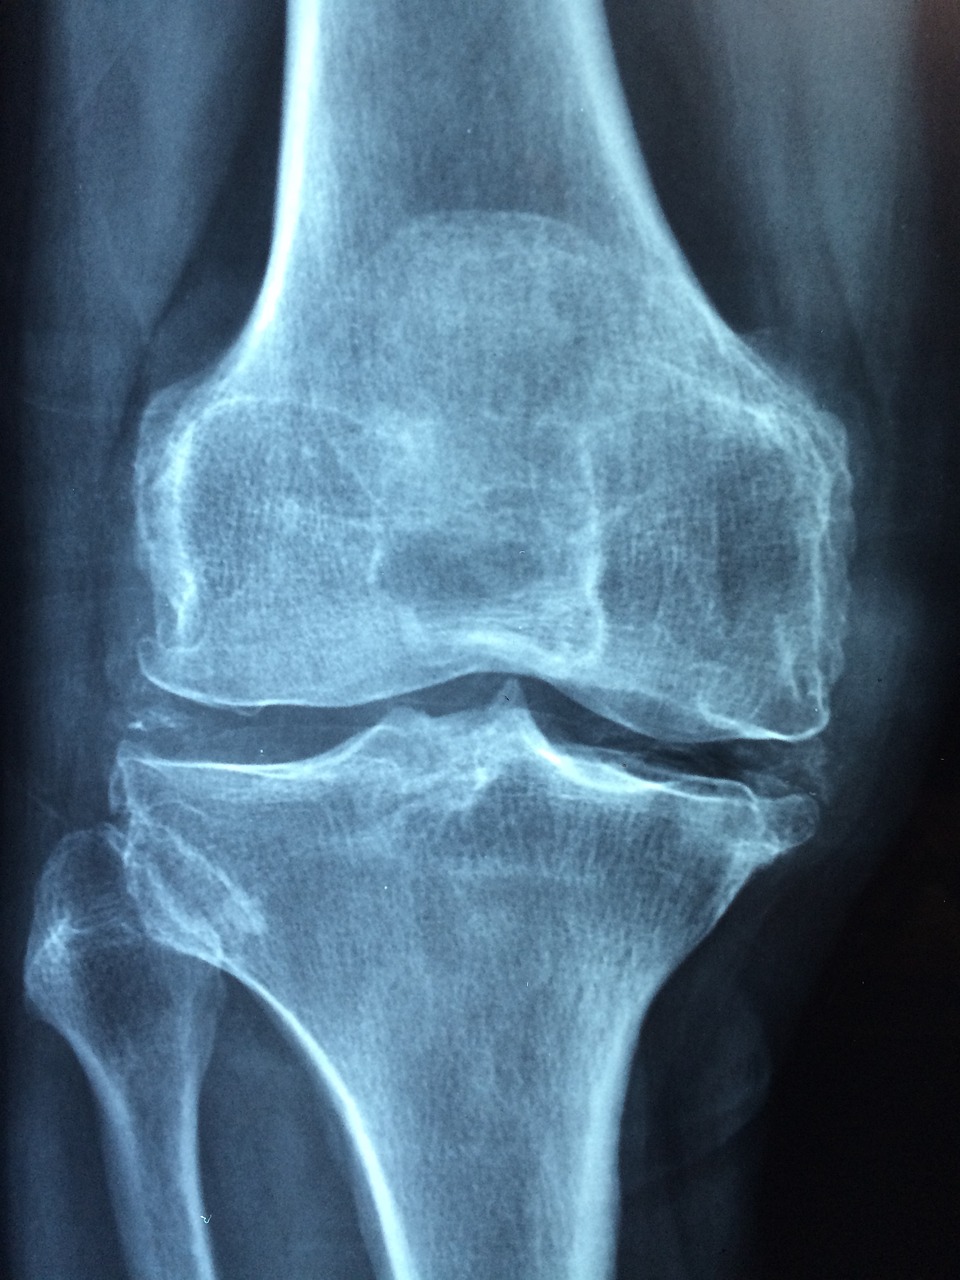

4. 신성 골이영양증 (Renal Osteodystrophy)

증상

만성 PTH 불균형으로 발생하는 뼈 질환.

뼈 통증, 골절 위험 증가, 성장 지연(소아의 경우).

장기적으로 기형적인 골 구조로 발전할 수 있음.

치료방법

PTH 수치 조절이 핵심: 비타민 D 제제 및 칼시민네틱스 병용.

칼슘·인 농도 유지: 이상적인 혈중 농도 범위로 관리.

필요시 뼈 대사 촉진제 또는 치료용 주사제 사용 가능.